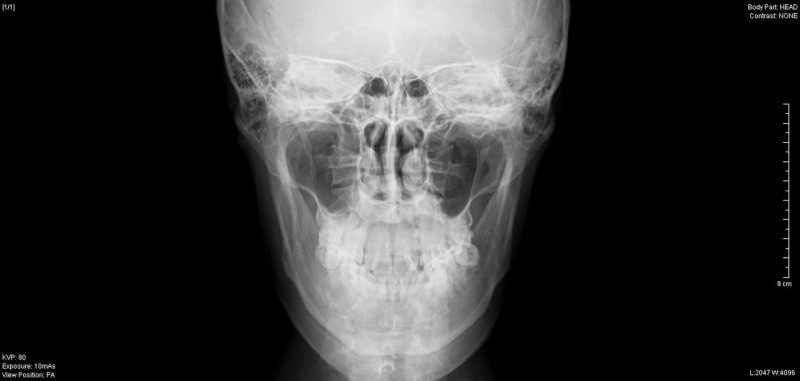

今回は年末に行った、オトガイ形成(顎の骨切り)

について取り上げます。

患者様は、20代 男性で、

顎を短くとがらせたいとの希望でした。

術前のレントゲン検査で最大9mm幅での切除が可能と判断し、

実際も同程度切除が行えました。